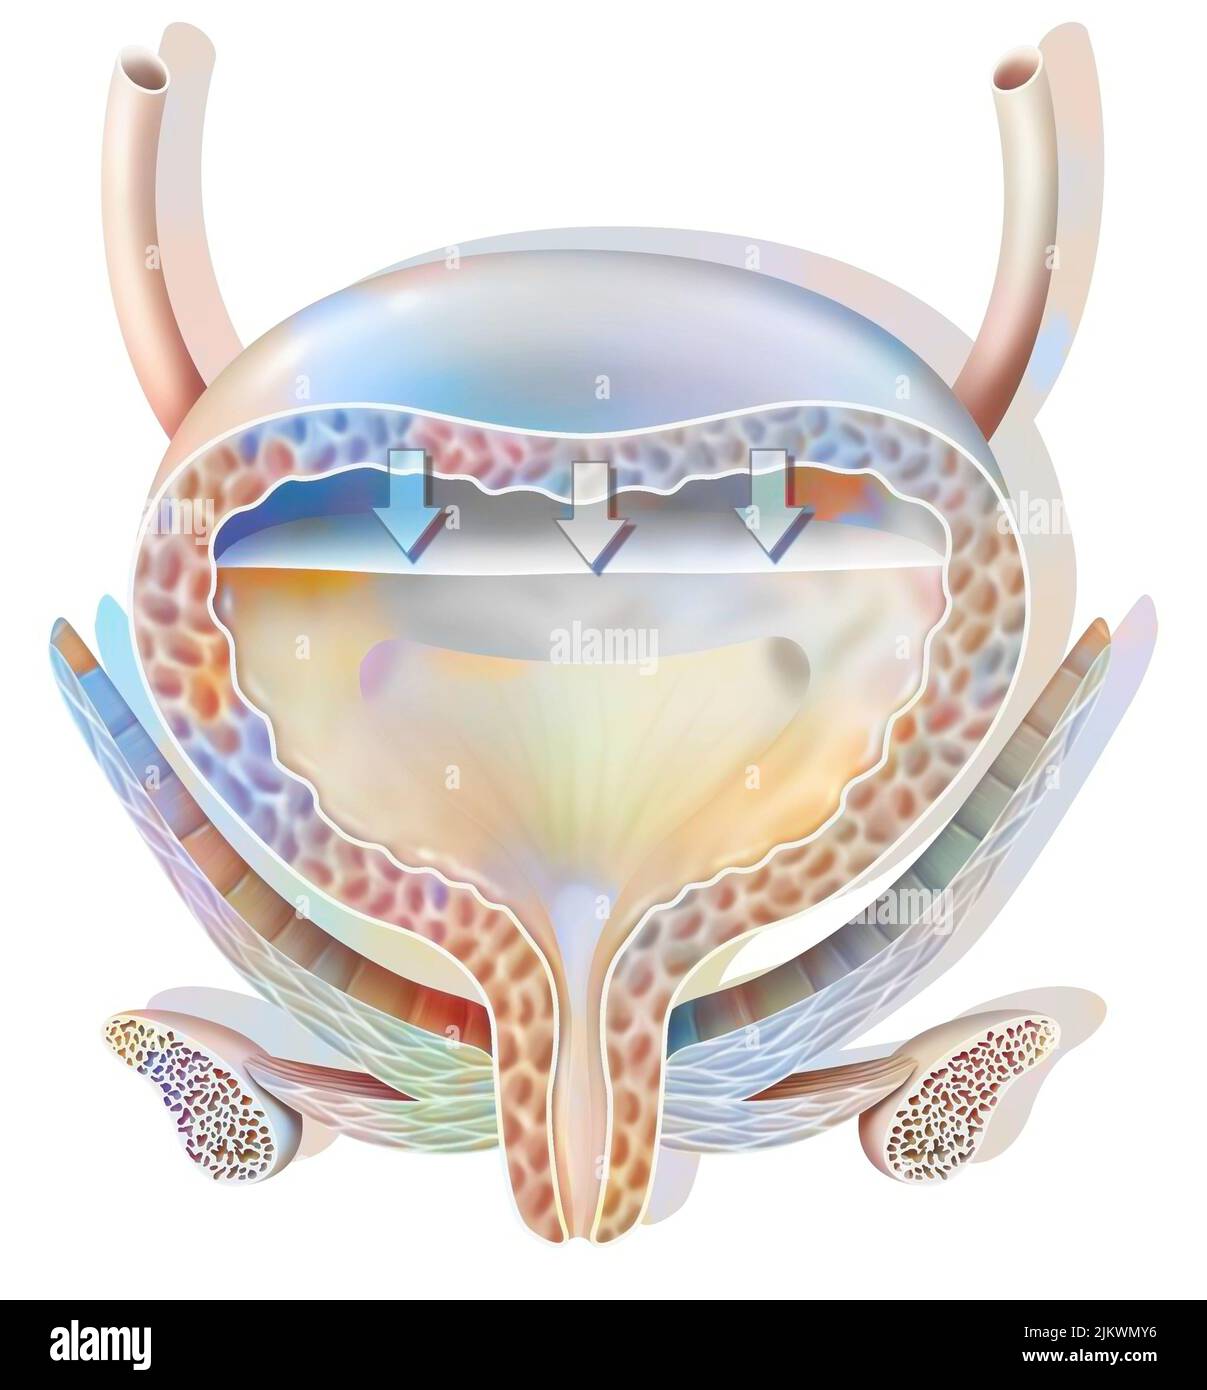

RF2JKWRM1–Vue antérieure des organes génitaux féminins avec vagin, utérus, trompes de Fallope, ovaires.